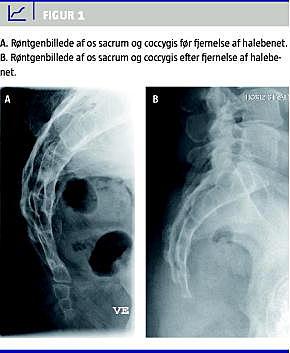

Os coccygis udgør den nederste del af rygsøjlen og består af fire til fem hvirvler, der er adskilt ved rudimentære disci, som hos flertallet vokser helt eller delvist sammen omkring puberteten eller senere [13]. Os coccygis er tilhæftningssted for musculus gluteus maximus, musculus iliococcygeus og de anococcygeale ligamenter. Første halehvirvel har en antydning af tværtappe og ledtappe og er via ligamenter forbundet med os sacrum, som det sent i livet kan fusionere med [5, 8, 13] (Figur 1 ).